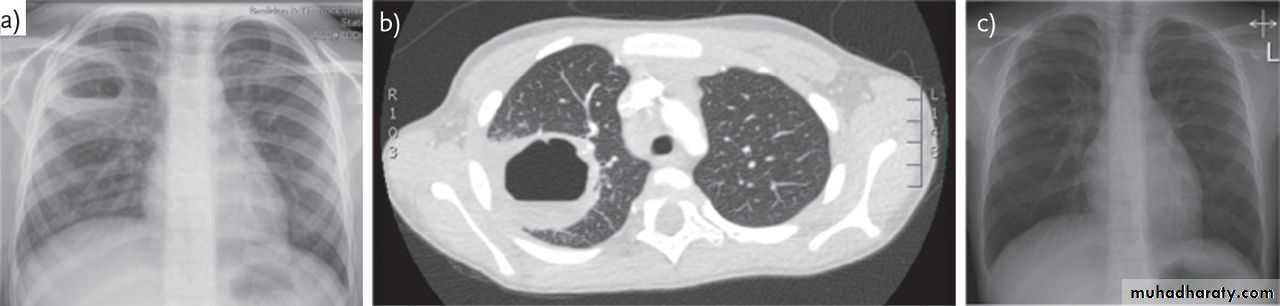

1-CXR:

PA and lateral views show effusion, air fluid level

• 6-CT scan

CXR : Air fluid level is only seen in upright film

CT san : clarify the diagnosis when the CXR is equivocal